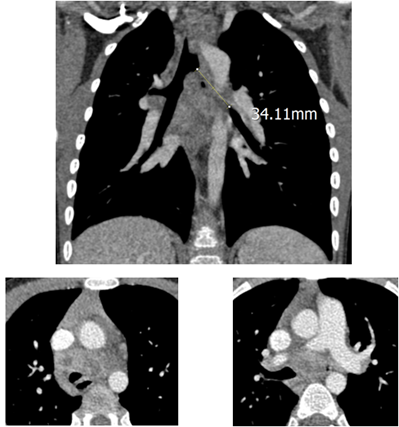

市公卫中心结核三病区曾经收治过一名可爱的藏族小姑娘,入院时有着严重的呼吸困难等症,胸部CT提示小姑娘的一侧主支气管重度狭窄(见下图)。

后来在全身抗结核治疗的基础上,小姑娘接受了经气管镜检查和介入治疗,镜下可见左主支气管肉芽增生阻塞管腔,立即予以冷冻联合局部用抗结核药物治疗(见下图)。